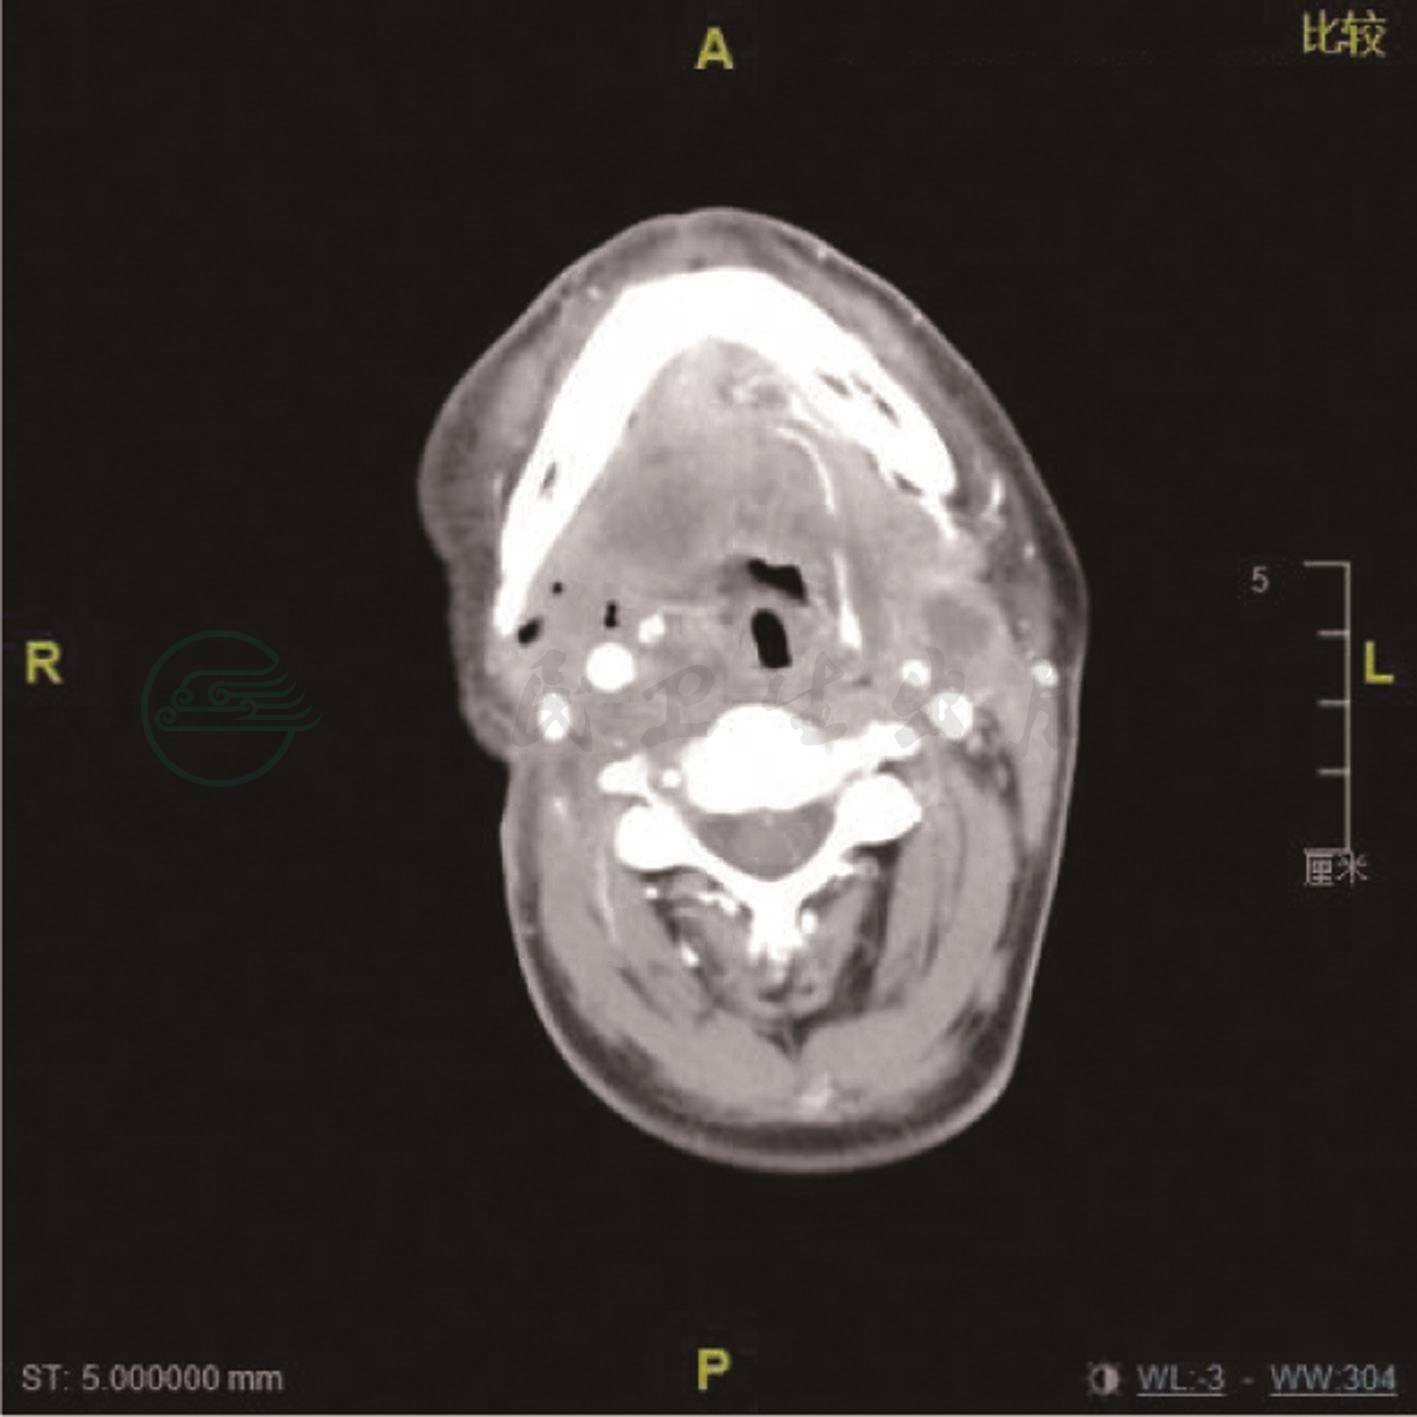

疗效评估:治疗后右颌下肿胀明显缓解,第2周期后评估为部分缓解(PR)(图2),后续原方案继续治疗;第4周期后评估为持续PR;第6周期后评估为肿瘤进展,疗效评估为持续PD(图3)。

图3 右舌颈术后复发靶向治疗中,右咽后及锁骨上、左侧颈上淋巴结转移可能

术区部分正常组织缺损,可见皮瓣修复,右侧颌下颈部软组织部分缺如,见斑片状致密填充物影。右咽后、右锁骨上、左侧颈上见肿大淋巴结,较大直径10mm,中央液化坏死